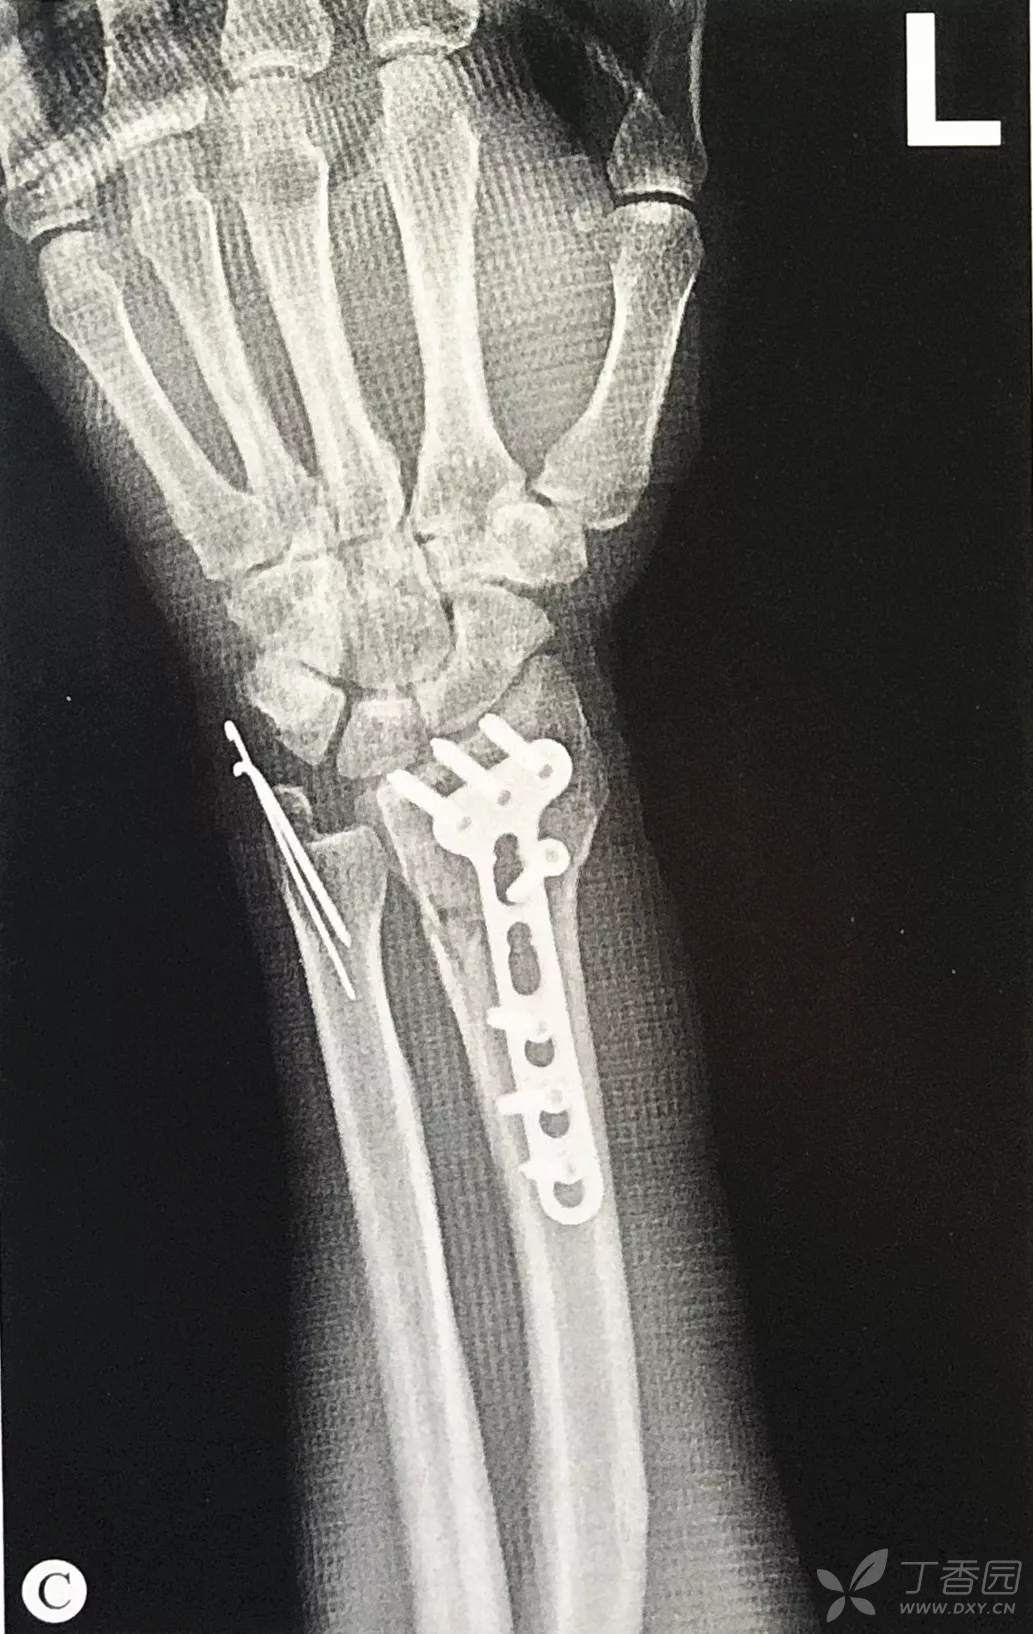

桡骨远端骨折手术技巧:切开复位内固定术

桡骨茎突的复位和固定:

对于移位的桡骨茎突骨折,由于肱桡肌的牵拉作用,可能影响复位效果,因此可以锐性分离肱桡肌附着于远端骨折块的附着点;或者在桡骨茎突置入克氏针作为摇杆协助复位和临时固定。

应用第二代、第三代掌侧桡骨远端钢板,可以置入桡骨茎突螺钉固定桡骨茎突骨块。

对于难以固定的桡骨茎突骨折,可以通过桡侧切口置入桡骨茎突钢板进行支撑(buttress)。

背侧唇骨块的复位和固定:

应通过掌侧钢板远端最靠尺侧的一枚螺钉固定,如果固定效果不满意,可以使用一枚克氏针辅助固定该骨块;

桡侧钢板远端螺钉位置:

McQueen等的研究表明,桡骨远端背侧皮质较薄,而关节面下的软骨较为致密,因此钢板应贴近桡骨远端从而使螺钉向背侧远端,使螺钉固定于软骨下骨而非置于背侧皮质。

桡骨远端骨折合并尺骨茎突骨折的处理:

- 当合并尺骨茎突骨折,特别是尺骨茎突基底部骨折时,桡骨远端骨折内固定后,检查下尺桡关节仍存在不稳,说明尺侧柱伴随严重损伤造成尺侧不稳,需行内固定恢复其稳定性:

辨认骨块,避免过多的剥离组织,固定方式可以选择克氏针张力带、微型螺钉或螺钉张力带技术。